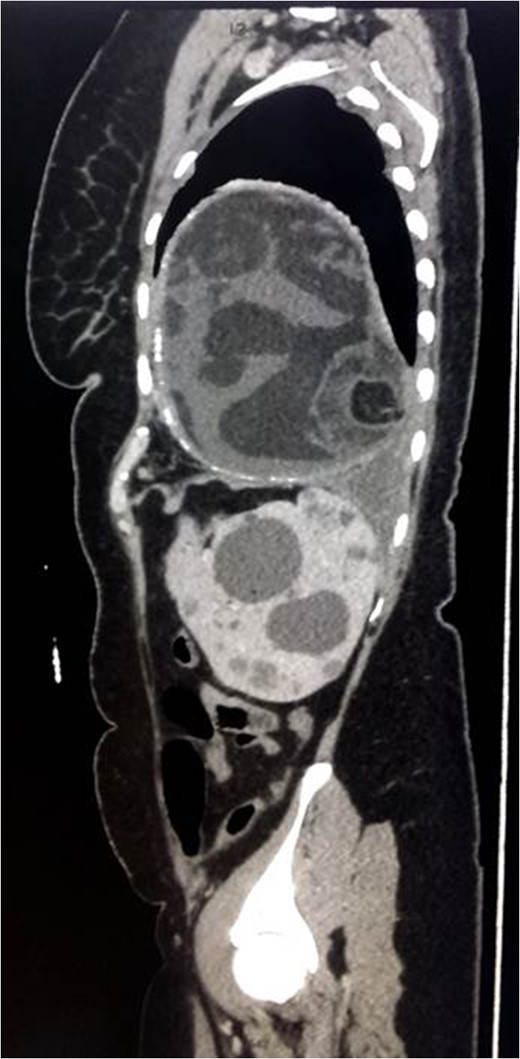

Chest x-ray showed well-defined huge opacity of most left hemithorax with a shift of mediastinum to the right (Fig. 1). CT chest/abdomen/pelvis with IV contrast revealed 20 × 15 × 18 cm3 well-defined mixed cystic lesion within the left lung containing multiple parts of the heterogeneous density with soft tissue elements and fat content. It also showed spots of wall calcification, where the lesion probably originated from the mediastinum, involving most of the left hemithorax. The mass compressed the mediastinal structures, great vessels, and airways (Fig. 2). It is surrounded by a consolidation collapsed with a marked shift of mediastinum to the right side (Figs 2 and 3). No mediastinal lymphadenopathy and the right lung was clear. The spleen was enlarged with multiple cysts that varied in size with no significant enhancement post IV contrast in arterial and portal phases (Figs 2 and 4). The liver was unremarkable. Hematological tests were within normal limits. Mantoux test and Sputum culture were negative.

The decision was to perform a standard left anterolateral thoracotomy to remove the thoracic tumor after expiration because the cystic tumor was found to be very congested and vulnerable to rupture during the extraction (Fig. 5). It emptied a large amount of thick, white/yellowish fluid and hair particles (Fig. 6). The size of the tumor was extremely large, although no invasion to the mediastinum, vessels or to the airway had occurred. The tumor detached from the phrenic angle, diaphragm and all of the surrounding structures without any bleeding, air leak or complications. A laparoscopic splenectomy was done in the same session, and the spleen was extracted through the old cesarean incision scar for cosmetic purposes; the spleen shows multiple cysts on both visceral and diaphragmatic surfaces (Figs 7 and 8).